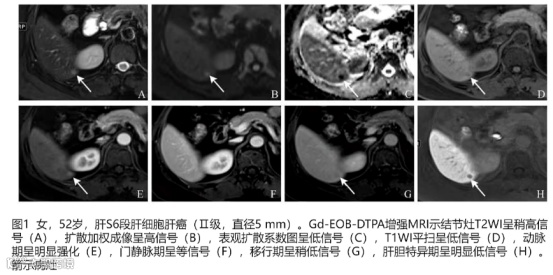

患者女性,63岁,甲胎蛋白升高。该病例若使用非边缘APHE+门脉期廓清将不能诊断为HCC,将移行期廓清纳入诊断标准后,则可以诊断为scHCC,且病理证实Edmondson-Steiner II级HCC。

a:T2WI高信号,b:DWI弥散受限,c:动脉期非环形强化,d:门脉期无明显廓清,e:过渡期低信号,f:移行期低信号,直径为7.3mm[5]。